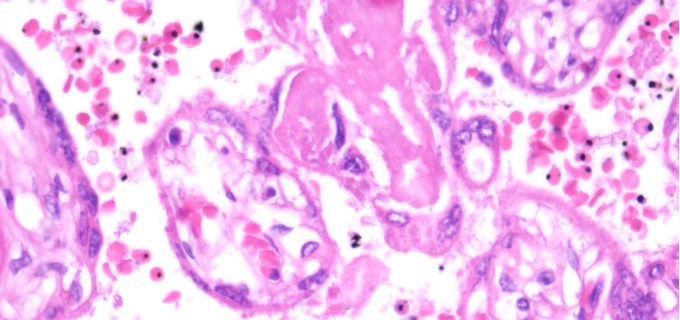

Foto: J. Ordi / P. Castillo

Per a això, els investigadors van estudiar les tendències parasitológiques, immunològiques i clíniques en gairebé 2000 dones embarassades que van acudir a l'Hospital Distrital de Manhiça (Moçambic) entre el 2003 i el 2012 en el context d'assajos clínics de tractament preventiu intermitent durant l'embaràs. Els científics van trobar que la prevalença d'infecció per P. falciparum al moment del part va disminuir d'un 33% a un 2% entre el 2003 i el 2010, per després incrementar-se fins a un 6% en el 2012. Els nivells d'anticossos contra el paràsit, incloent aquells que es generen específicament durant l'embaràs i que ajuden a limitar la densitat del paràsit en la placenta, van seguir tendències similars a la prevalença de malària. Comparat amb el període d'alta transmissió entre el 2003 i el 2005, la densitat parasitaria en les dones infectades va ser major en el període 2010-2012 i el desenllaç del part va ser pitjor, ja que els nivells d'hemoglobina de la mare i el pes del fetus es van veure significativament reduïts.